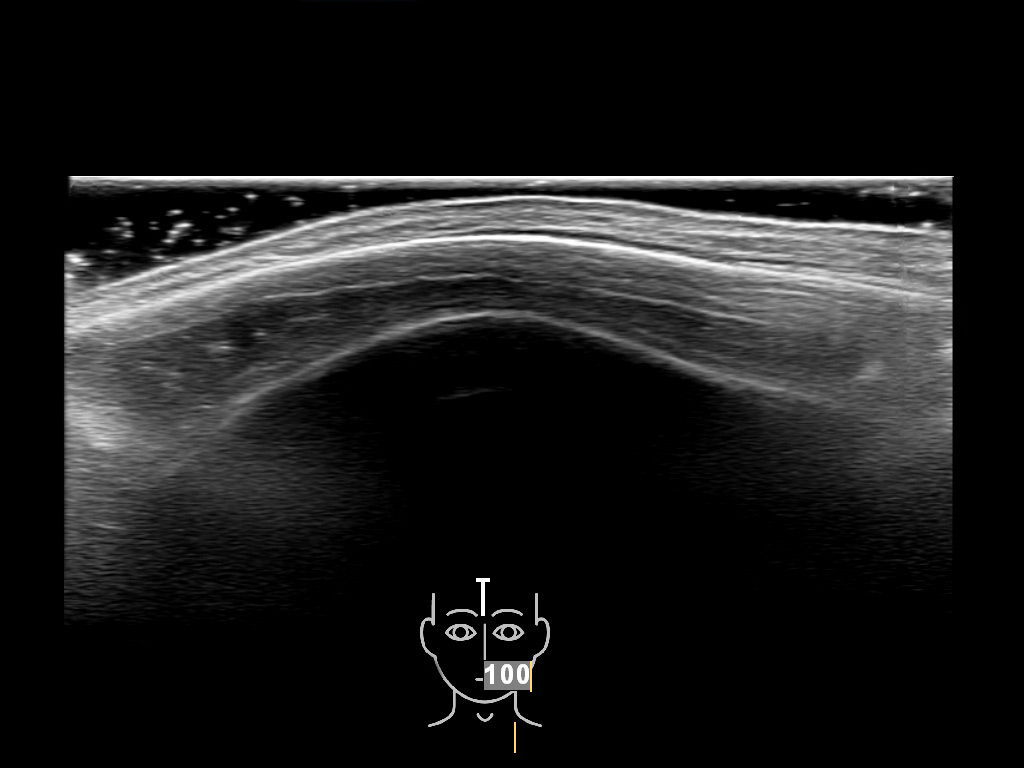

In this section you will learn more about the different layers of the face with the use of ultrasound. When you click on the secondary ultrasound image, you will see the different structures as an overlay. This will help to train yourself to recognize the different layers of the face.

Study the first image to recognize the different layers. If you are sure about the layers, swipe to the second image to view the answer (if applicable).